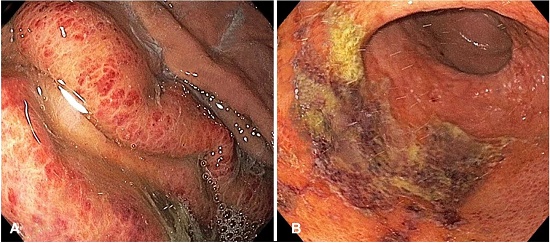

Upper gastrointestinal (GI) endoscopy demonstrated severe mucosal erythema, multifocal superficial ulcerations with purulent exudates in the gastric body and antrum, and scattered blood clots, indicating recent hemorrhage (Figure 2).

The patient continued treatment with IV piperacillin-tazobactam and clindamycin for 8 days. Repeat CT scan and endoscopy 5 days after the initial diagnosis demonstrated apparent improvement of gastritis with gastric biopsies being negative for organisms. Some improvement of the upper GI symptoms was noted, but there was persistent C difficile-negative diarrhea, rectal bleeding, and pancolitis. The patient received additional treatment with vancomycin, micafungin, and metronidazole, with no clear improvement. Subsequently, the patient had severe anion gap metabolic acidosis, uremic pericarditis, encephalopathy, multifocal renal infarctions requiring hemodialysis, coagulopathy, shock, and multiorgan failure. Persistent leukocytosis was noted, reaching 47.4 K/mm3 before death.